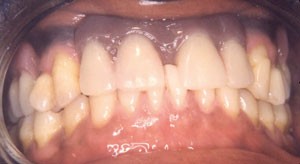

Motif de consultation et histoire de la maladie Cette patiente âgée de 39 ans, désireuse d’améliorer son sourire et son...

ODF